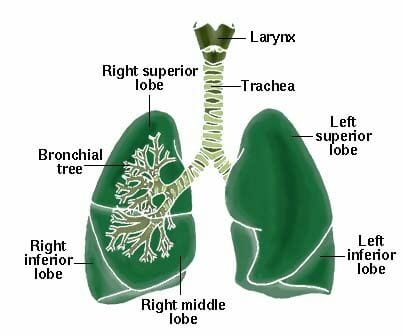

In de jaren tachtig werd hiervoor een oplossing gevonden: het transplanteren van longen en hart samen. In 1981 is de eerste succesvolle hart-longtransplantatie uitgevoerd. Het transplanteren van de twee organen samen zorgt ervoor dat de getransplanteerde longen en luchtpijp voldoende bloed ontvangen om te kunnen genezen.

De lijst van problemen en beperkingen is lang. Het vinden van longen en harten van donoren kan zeer moeilijk zijn, omdat de longen van slachtoffers van ongevallen, bij wie hersendood wordt vastgesteld, vaak beschadigd zijn. Om bruikbaar te zijn moeten de longen passen bij de lichaamsgrootte van de ontvanger, er moet overeenstemming zijn met het bloedtype en met de eigenschappen van de weefsels (compatibiliteit). De laatste tijd zijn er door gebruik te maken van nieuwe immunosuppressiva en nieuwe technieken met succes veel transplantaties van twee longen en één long verricht, waardoor de mogelijkheid bestaat dat het hart en de longen van één donor kan helpen de levens van drie mensen te redden in plaats van maar van één. Wanneer het hart van een patiënt bij wie een longtransplantatie noodzakelijk is gezond is, kan dit bij een hart-longtransplantatie vaak weer als donorhart dienen voor iemand die daaraan behoefte heeft.

Een longtransplantatie is een riskante, kostbare en zeer gecompliceerde ingreep, die uitsluitend wordt verricht bij patiënten voor wie de enige hoop te blijven leven een transplantatie is en in gevallen waarin de kans op succes groot is. De meeste ontvangers van een succesvolle longtransplantatie blijken na hun herstel op korte termijn een betrekkelijk normaal leven te kunnen leiden. De resultaten op lange termijn zijn nog niet bekend.